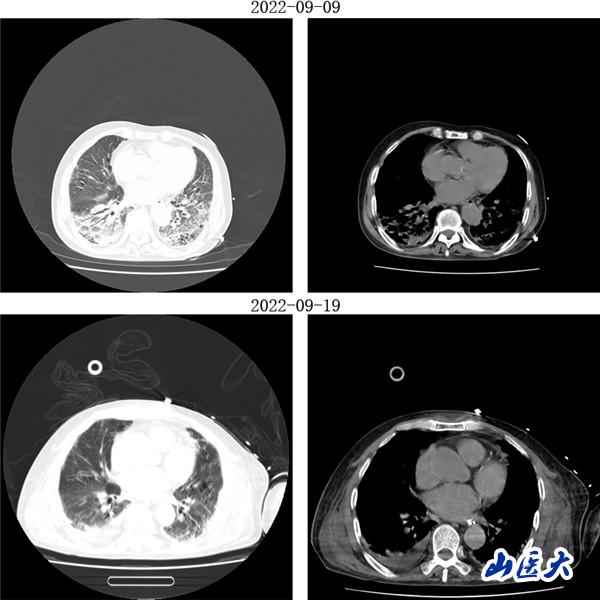

重症医学科三病区张文凯主任团队深入分析了两位患者的病情。考虑到两名老年患者均已出现急性呼吸窘迫综合征,决定采用俯卧位通气技术为他们治疗。在张文凯主任的指导下,侯林义主治医师带领张承、孙洁住院医师对女性患者经俯卧位通气治疗,92小时后复查胸部CT,双肺明显好转,氧合指数由90上升至300mmHg以上,吸氧浓度由100%降至35%,ARDS明显改善;对男性患者,采用联合持续性血液滤过(CRRT)治疗方案,经俯卧位通气治疗66小时后复查胸部CT,显示明显改善,同时氧合指数由102上升至360mmHg左右,吸氧浓度需求下降至40%,全身水肿情况也明显减退。

(女性患者治疗前后胸部CT对比)